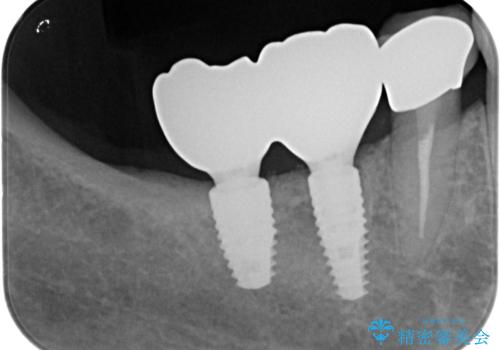

最新の症例

Latest cases